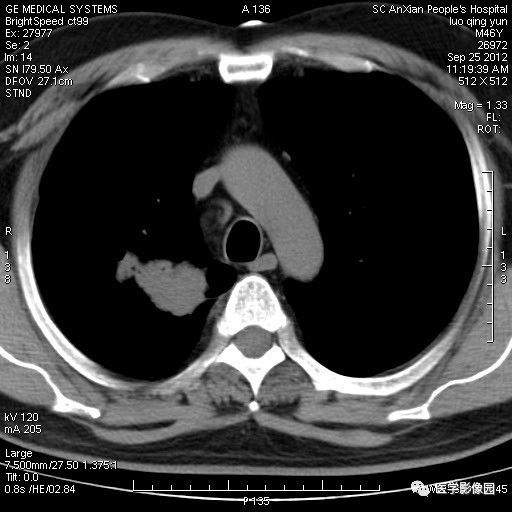

影像学表现:右上肺见不规则团块状高密度阴影,略有分叶级毛刺,边缘模糊,邻近胸膜增厚,增强扫描呈轻中度强化。

诊断结果:右上肺炎性假瘤

本病影像学表现无绝对特征性。单发多见,多位于肺表浅部位,多呈圆形或椭圆形,直径多在2-5cm或更大;多有假包膜,边缘多清晰光整,有时也毛糙,并可有分叶或毛刺;邻近胸膜局限性增厚、牵拉,病灶边缘呈桃尖样突起即桃尖征(尖端指向胸膜);增强扫描多呈中度均匀强化,持续时间较长。亦可显著强化。